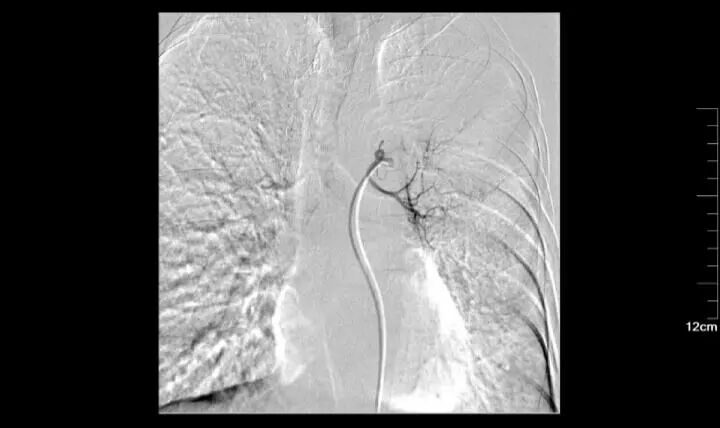

一 局部灌注化療

傳統(tǒng)的全身化療是對(duì)付腫瘤很常用的辦法,但是,傳統(tǒng)化療所帶來(lái)的副反應(yīng)讓患者痛苦不堪。有沒(méi)有什么方法既可以對(duì)付腫瘤,又能讓患者不那么痛苦呢?那就是局部灌注化療!特別適合于局限生長(zhǎng)的腫瘤。介入醫(yī)生可以將一根很細(xì)的特制導(dǎo)管在影像設(shè)備的引導(dǎo)下插到腫瘤的供血?jiǎng)用},再通過(guò)導(dǎo)管直接往腫瘤里注入化療藥物。

腫瘤生長(zhǎng)需要由供血?jiǎng)用}提供營(yíng)養(yǎng)物質(zhì),介入醫(yī)生可以將特制的導(dǎo)管送至腫瘤的供血?jiǎng)用},然后通過(guò)導(dǎo)管注入栓塞物質(zhì),把腫瘤的供血?jiǎng)用}完全栓塞住,讓腫瘤沒(méi)有營(yíng)養(yǎng)供應(yīng),在實(shí)際工作中,常常把化療藥物與栓塞物質(zhì)混合,從而在栓塞血管的同時(shí)不斷釋放化療藥物持續(xù)殺死腫瘤細(xì)胞,效果更加顯著,就是老百姓常說(shuō)的把腫瘤餓死。

55歲男性,左肺鱗癌,行三次左肺支氣管動(dòng)脈灌注化療+栓塞術(shù)后,治療縮小,結(jié)合局部放療,病情控制可。